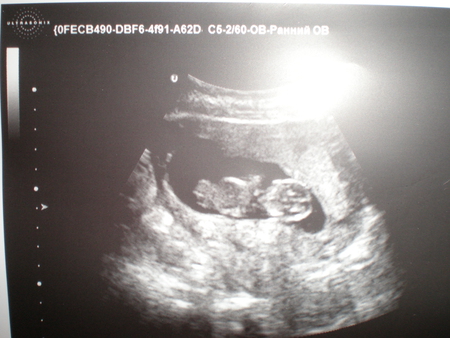

Первое УЗИ